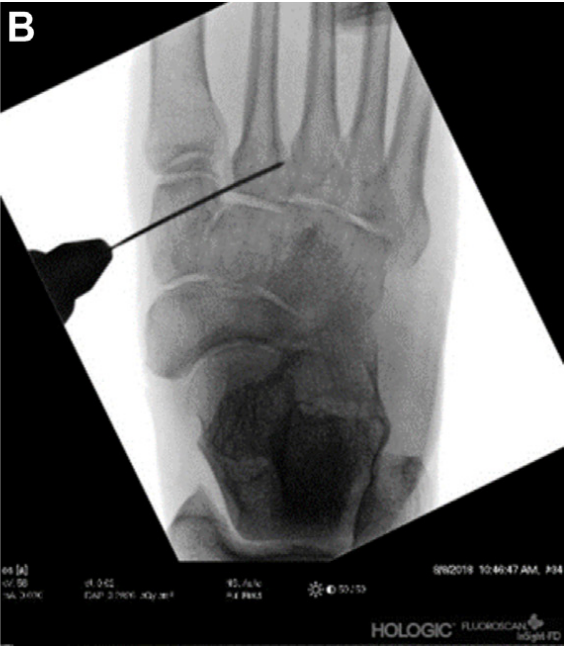

▲图示麻醉状态下,通过术中透视观察到Lisfranc关节分离情况。

麻醉满意后,患者取仰卧位,大腿根部应用气压止血带。术前,在C臂机下透视评估Lisfranc关节分离情况。在第二、三跖骨基底之间做纵向背侧皮肤切口,在外侧楔骨上方做内侧皮肤切口。采用锐性分离法,在拟放置 TightRope:tm:的区域掀起内侧楔骨后表面的骨膜,形成一个凹陷,以便后续与骨面精准贴合并埋藏缝线结。在透视确认下,将第二跖骨基底复位至正常解剖位置。随后,在透视引导下,沿Lisfranc韧带走向从内侧楔骨向第二跖骨基底钻入导针。